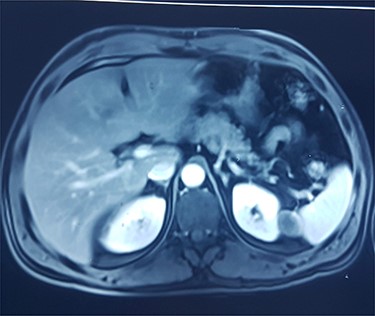

This is a 50-year-old patient with a history of medically treated renal lithiasis, who consults for left low back pain. The patient was apyretic and reported no urinary symptoms. The clinical examination was without any particularities. There was no organomegaly or lumbar contact on bimanual palpation. Biologically, there were no abnormalities, including no biological inflammatory syndrome, and renal function was preserved. The urine culture was sterile. Renal ultrasound revealed a 3-cm left cortical renal mass with moderate vascuarization. Abdominal CT scan confirmed the presence of a heterogeneous Bosniak type 3 cystic mass having a thickened wall (Fig. 1). Abdominal MRI showed a left polar cyst having an exophytic development and a thickened wall with spontaneous T2 hypointensity and T1 hyperintensity without any pathological enhancement after Gadolinium injection (Fig. 2). The retained diagnosis was an hemorrhagic benign cyst. At multidisciplinary meeting, the decision was to perform an MRI 3 months later which showed a left medio-renal cortical cystic mass measuring 24 × 28 mm having a T1 hyperintensity and heterogeneous T2 hypointensity, with a thickened wall mildly enhanced after contrast injection evoking a Bosniak type-3 hemorrhagic cyst. Seeing the MRI results, we decided to perform a left tumorectomy. Pre-operatively, the perirenal tissues were inflammatory and adherent to the capsule, a complete dissection of the kidney was performed allowing the identification of the tumor which was of a 3-cm diameter and a partially exophyctic development, then we cut the tumor with a 2-mm surgical margin. No urinary tract leakage was observed. Finally, renorraphy was performed in two plans using Vicryl 2-0 and 1 (Ethicon, Cincinnati, OH, USA). After confirming the lack of active bleeding, we placed a drainage tube and closed the incision. The total operation time was 1 h 45 min, with 18 min of selective clamping. The post-operative course was uneventful, and the patient was discharged 2 days post-operatively. The histopathological examination revealed a 2.5 × 2.7 cm necrotic lesion with an inflammatory interstitial infiltrate dissociating the epithelial structures (Fig. 3). The retained diagnosis was a pseudo tumoral Xanthogranulomatous pyelonephritis. The CT performed 3-months after surgery showed no abnormalities.

MRI showing left polar cyst having an exophytic development and a thickened wall with spontaneous T2 hypo-intensity and T1 hyperintensity.